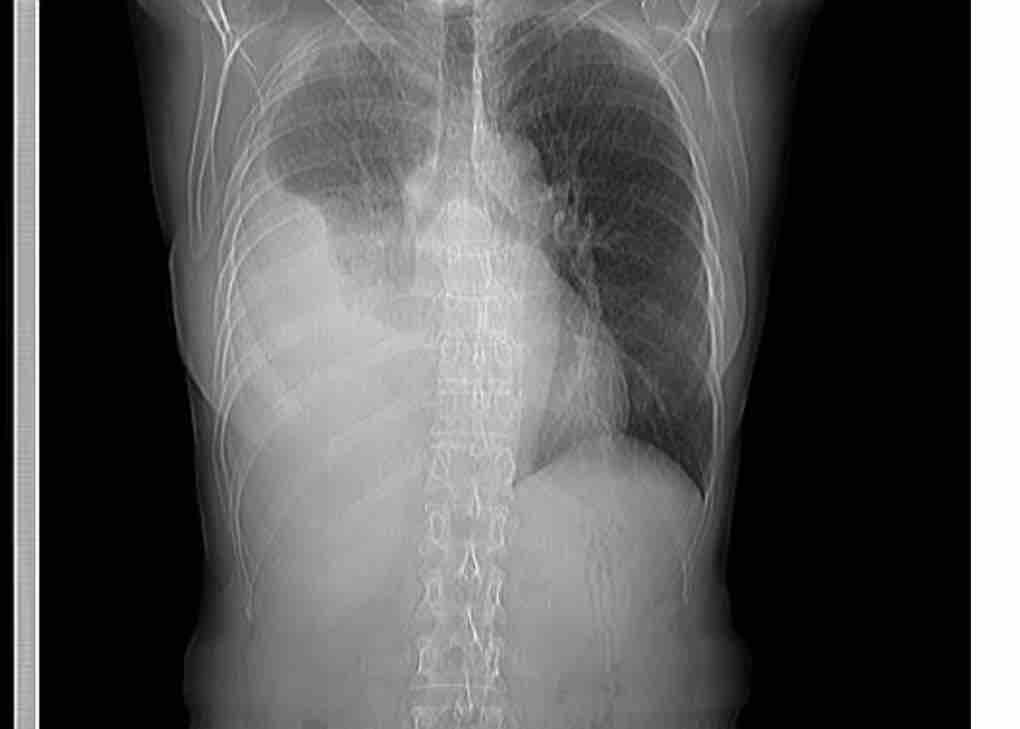

Desde que su malestar inició hace ya tres meses, la salud de Aura se ha venido en decadencia, con un malestar constante, dolor en el área pulmonar, poca oxigenación de la sangre e inclusive la acumulación de líquido en su pulmón (derrame pleural).

Since her discomfort began three months ago, Aura's health has been in decline, with constant discomfort, pain in the lung area, little oxygenation of the blood and even the accumulation of fluid in her lung ( pleural effusion).